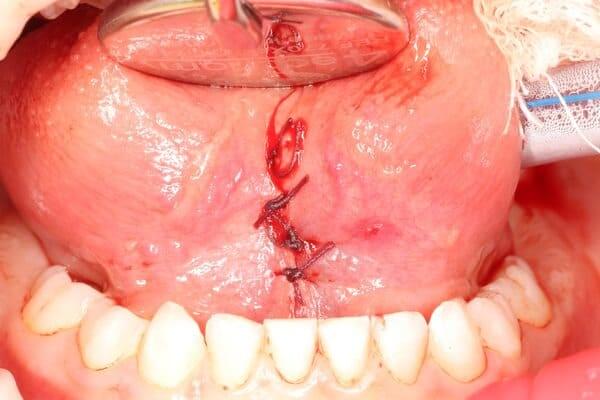

Травма постійних зубів. Олег Ковнацький.

Дівчинка 7 років, перше вересня, гойдалка… Вивих постійного зуба: якщо в такій ситуації зволікати, дитина може втрати постійний зуб назавжди. Батькам порекомендували нас і пацієнти одразу приїхали. Через складність і травматичність процедур вирішено проводити лікування в анестезіологічному супроводі. Зуб поставлений на місце (репонований), проведена хірургічна обробка і ушивання рани губи. Останнє фото через рік після травми: зуб на місці і корінь продовжує розвиватись, губа повністю загоїлась

Видалення надкомплектних зубів. Бродик Богдан.

Надкомплектні зуби — це той випадок, коли зубів у зубному ряду є більше, ніж задумано. У такому випадку вони заважають повноцінному прорізуванню основних зубів та створюють ортодонтичні проблеми. Вихід у даному випадку — видалення надкомплектних зубів з подальшим ортодонтичним лікуванням. Завдяки злагодженій роботі з анестезіологічною командою проведене делікатне видалення надкомплектного зуба, ушивання рани, і тепер юна пацієнтка готова до того, аби її посмішка формувалась належним чином.